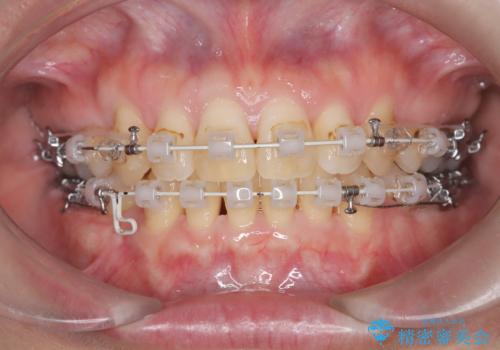

- 前歯の凸凹と前突感を改善するため、上下左右の4番を抜歯し、空いたスペースを利用して前歯を後方へ下げる審美ワイヤー矯正を計画しました。抜歯後は透明で目立ちにくい審美ブラケットを装着し、ワイヤーを用いて徐々に歯列を整えます。毎月1回の調整を通じて歯並びの変化を確認しながら、丁寧に矯正を進め、約2年で理想的な歯列と噛み合わせを完成させることを目指します。

前歯が前に出ていることや歯並びの凸凹が気になるという主訴でした。十分なスペースを確保するため上下左右の第一小臼歯(4番)を抜歯し、そこに前歯を移動させて整列を行いました。矯正装置には目立ちにくい透明なブラケットを選択し、見た目のストレスを軽減。矯正期間中は定期的な通院でワイヤーを微調整し、無理なく確実に歯を動かしました。治療後は前歯が自然な位置に下がり、口元の突出感が解消されるとともに、美しく整った口元に仕上がり、患者様にも大変喜んでいただけました。